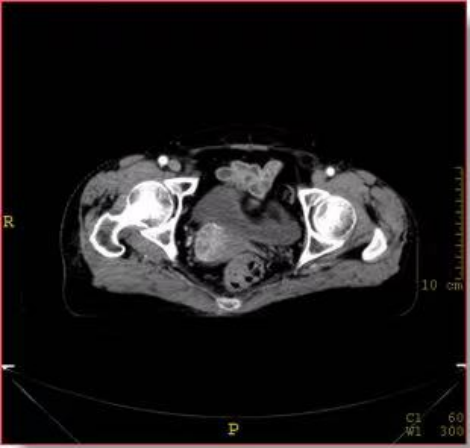

四是应用范围较广。大孔径CT由于孔径大,方便操作,图像显示清晰,不仅用于肿瘤放疗诊断治疗,同时也用于CT引导下肿瘤定位、穿刺活检及介入治疗等方面。

肿瘤介入——消融